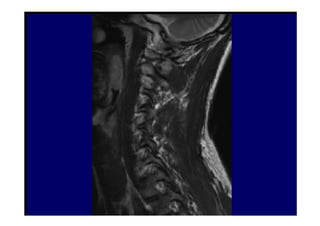

• 3. Ressonância Magnética

Opção preferencial para detecção de

patologias de partes moles tais como hérnia

de disco e tumores. Estudo realizado em 100

pacientes com doenças na laringe, sem

queixas clínicas relacionados à coluna cervical,

evidenciaram 20% de lesão discal em

pacientes entre 45-54 anos e 57% com mais de

64 anos.